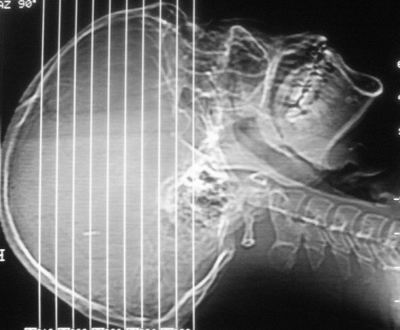

患者,男,30岁,右侧面部麻木,右上肢活动受限27小时。pe:神清、呼吸平稳,口角左歪,右上肢活动受限,右手掌握力消失,右侧躯体痛觉减退。

第一次颅脑ct扫描:左侧额顶叶血肿。